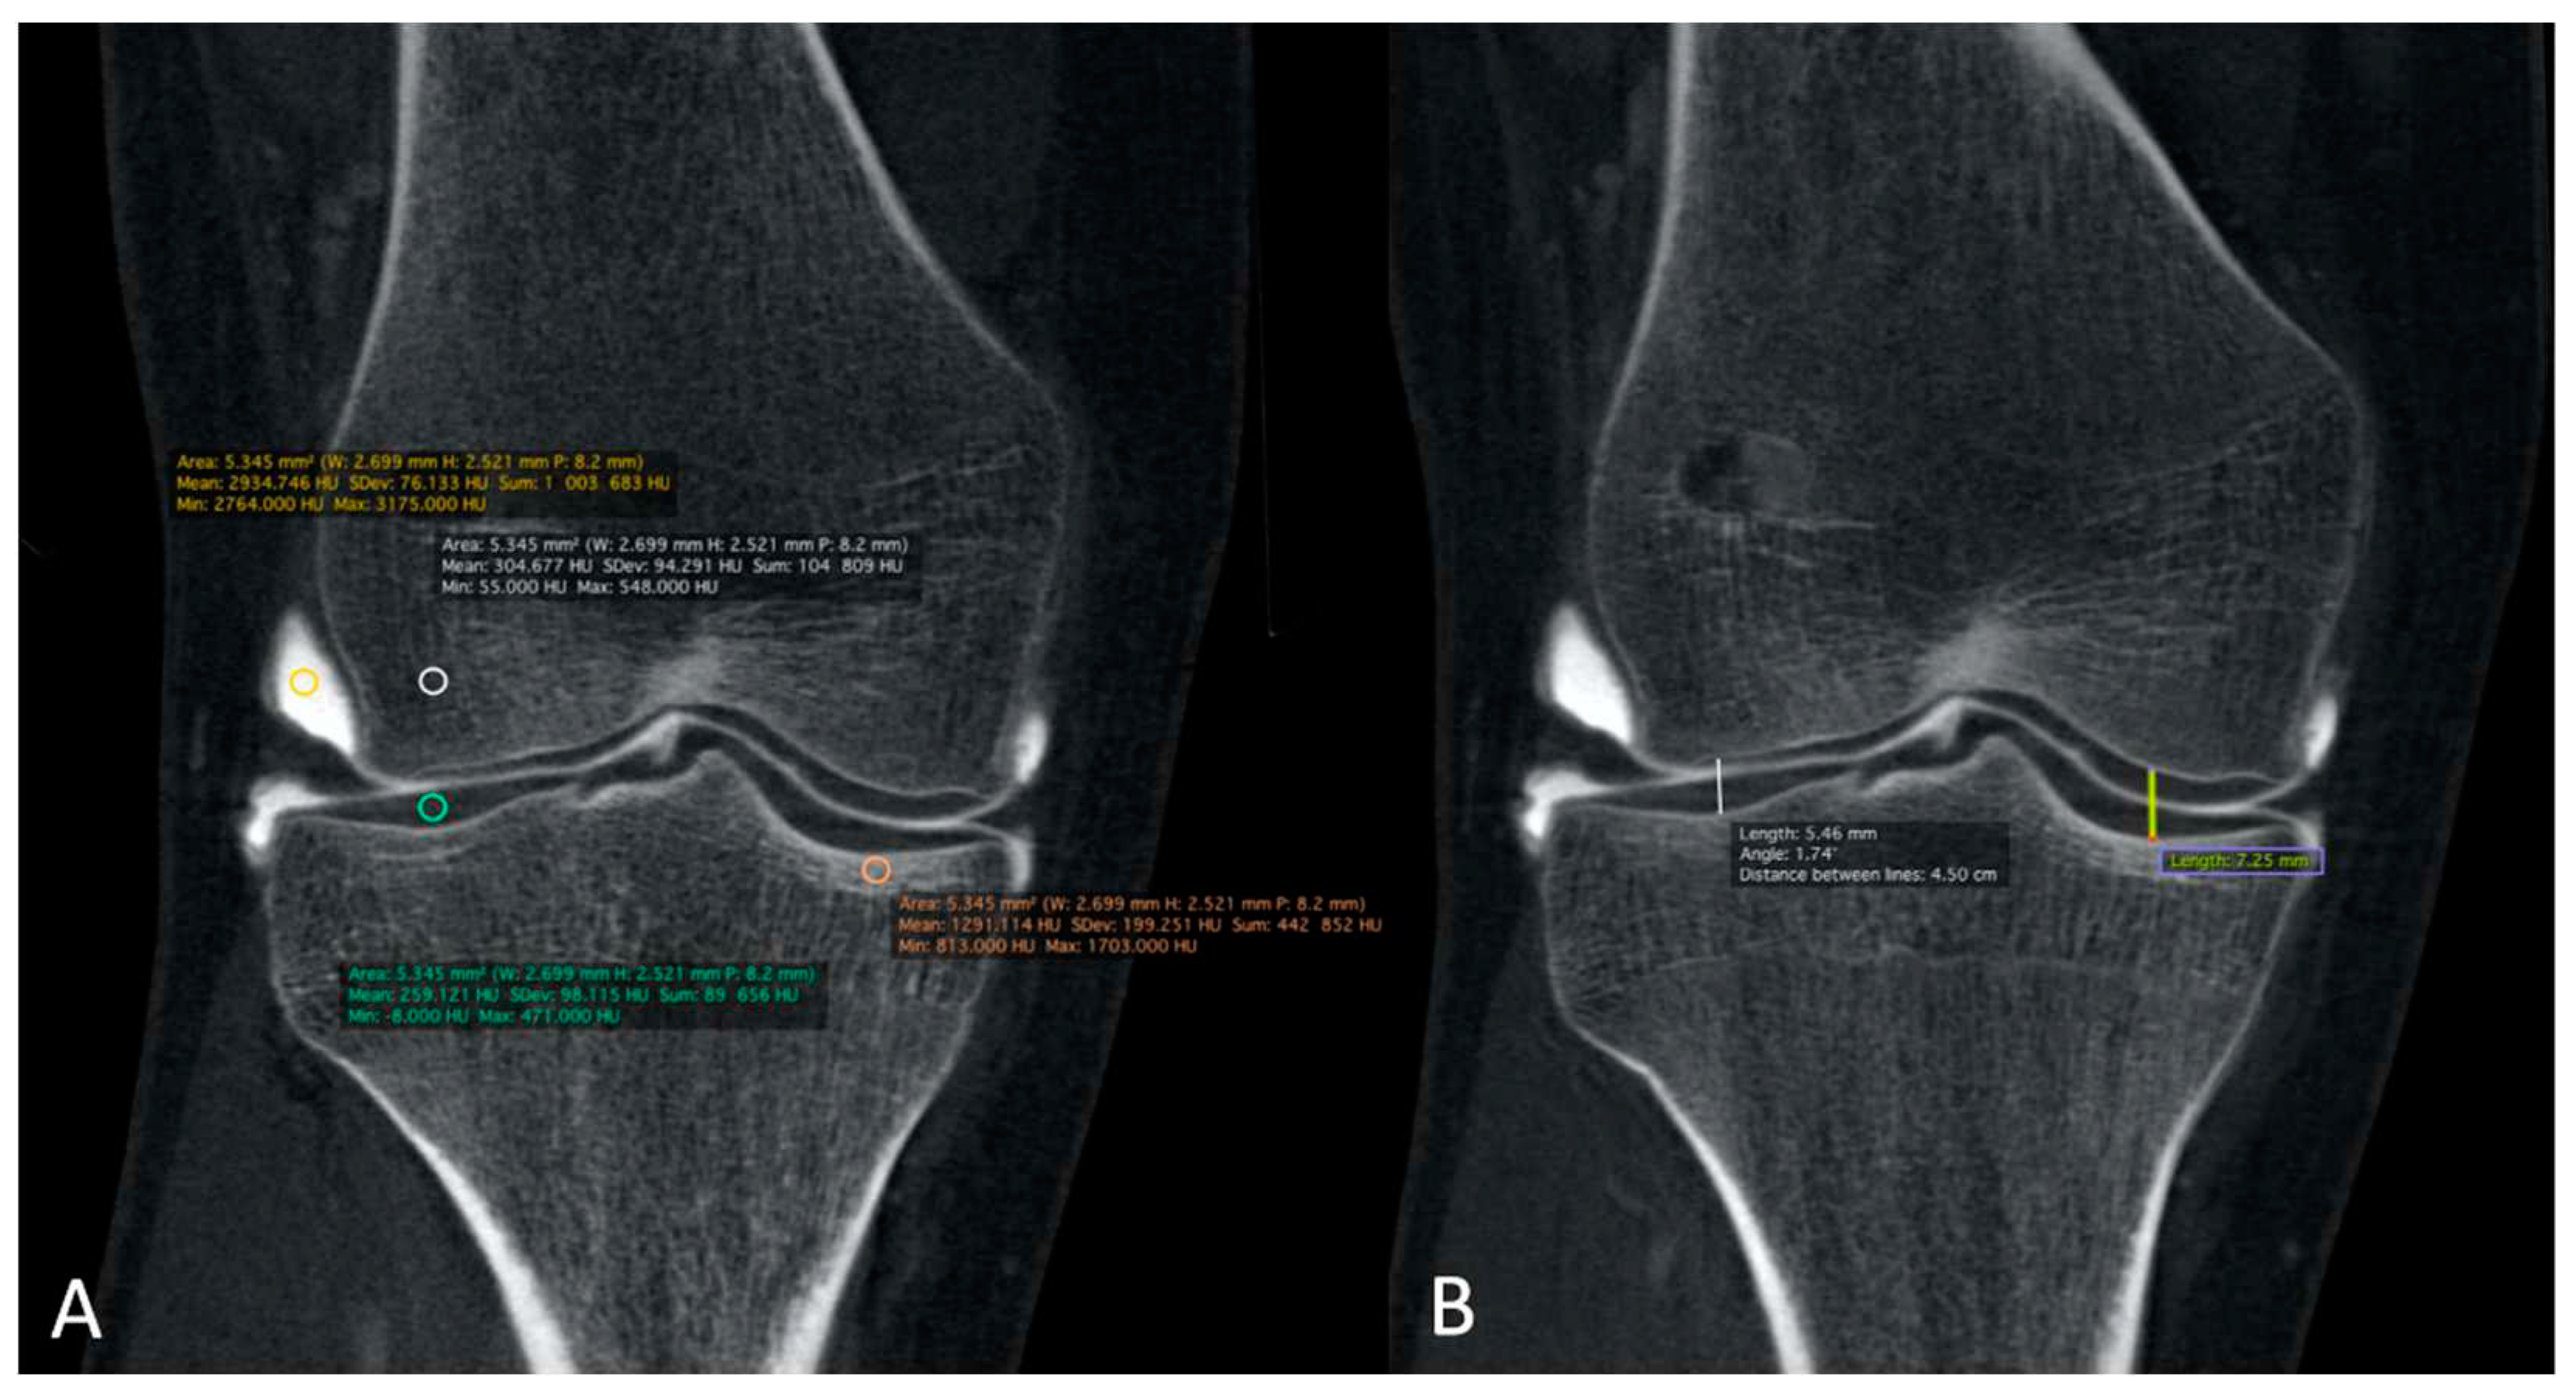

The correspondence between electronic densities and the HU was evaluated using a standardized CIRS-062MA (Norkfold, Virginia, USA) phantom (Figure 3) for the CBCT images reconstructed with the two available reconstruction algorithms: MBIR 1 and MBIR2. The results were compared to the HU obtained from the two MDCT (SOMATOM Definition Flash Siemens Healthcare and Discovery 750 HD GE Healthcare) available in our department. The phantom comprises nine inserts with different materials corresponding to different electronic densities (Figure 3A). The reproducible region of interest (ROI) (size and seat) was placed in all nine inserts (Figure 3B), with three measurements for every item. Then, we analyzed the HU for all 32 CBCT-As in the coronal plane for CM, the trabecular subchondral bone, cortical bone, and cartilage densities after application of the MBIR2. ROI were also placed in all cases, with three measurements for every item (Figure 4A). The mean was reported for statistical analysis.

Finally, MJWs were calculated, of the lateral and medial sides for the knee and center of the radio-carpal joint in the wrist or talocrural joint in the ankle, the tibio-talar joint in the ankle, and the femoro-tibial joint in the knee (Figure 4B) and compared with the corresponding DR images.

Figure 4. The HU numbers and JSN of all 32 CBCT-As were analyzed in coronal plane after application of MBIR2. Here, example of a right knee is shown. HU for CM, trabecular and cortical sub chondral bone and for cartilage densities were reported. ROI were also placed with three measurements for every item (A). The MJW was evaluated with the MJW at the lateral and medial side of the femoro-tibial joint (B). HU: Hounsfield unit; CBCT-A: cone-beam computed tomography arthrography; ROI: region of interest; MJW: mean joint width. HU: Hounsfield unit; CBCT: cone-beam computed tomography; MDCT: multi-detector computed tomography; ROI: region of interest.

The qualitative image analysis was excellent in all CBCT-A cases, with an excellent inter-observer concordance (kappa=1), as shown in Figure 4 and Figure 6. Twenty-four patients had an OA diagnosis (KLC ≥2) with the CBCT-A, and twenty-one were subclassed with DR. No statistically significant difference was observed in terms of sclerosis (p=0.29) and erosion (p=0.184) between both modalities. Examples of OA underestimation, with DR compared with CBCT-A are shown in Figure 6.

Concerning the quantitative image analysis, OA under-classification was noticed with DR regarding MJW (p=0.02), detection of osteophytes (<0.0001), and KLC (P<0.0001), as shown in Table 3.

Table 4 summarizes the results obtained from the calibration of the HU with the standardized phantom. Measurements in both the MDCT (Siemens and GE) revealed similar densities in all tissues analyzed. For CBCT, the HU did not correspond to the usual values obtained for the MDCT, with a greater mean deviation obtained with the CT HU for the MBIR1 than MBIR2. The mean HU calculated for the CBCT-A was 1966 for CM, 328 for trabecular bone, 812 for subchondral cortex, and 330 for cartilage. We focused on bone density, as no normal values were found in the literature for cartilage; regarding CM, the contrast was diluted with the joint effusion in many cases. We noticed that the HU of CBCT-A measured for trabecular bone and cartilage were similar and correspondeded to the bone density values of 200mg/cc for the MDCT, with either MBIR1 or MBIR2 (236-298HU). The HU of subchondral cortical bone on CBCT-A was similar to the HU of bone with a density of 80mg/cc on MDCT, particularly with MBIR2 (Table 4).